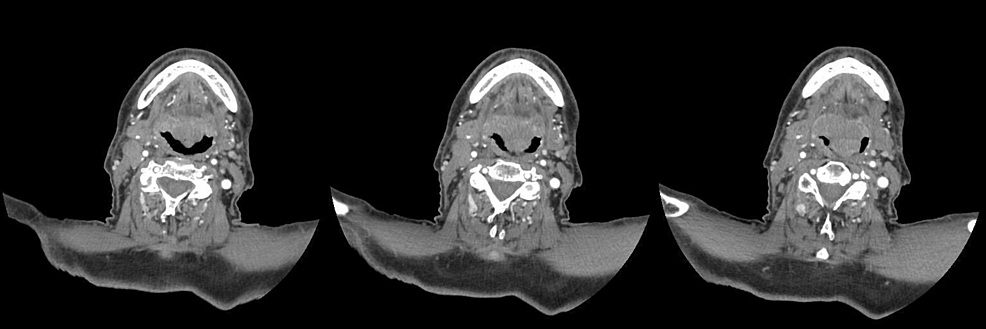

All four patients had an interdental distance greater than 35 millimeters; thus, we chose to proceed with the use of the videolaryngoscope instead of the fiberscope. These patients, all considered candidates for general anesthesia, presented a reduced respiratory space on fibroscopy, with a tumor mass partially obstructing this space as well as fragile tissue. Notably, in Case 1, an axial CT scan of the neck revealed the presence of supraglottic cancer at three different levels (Figure 2).